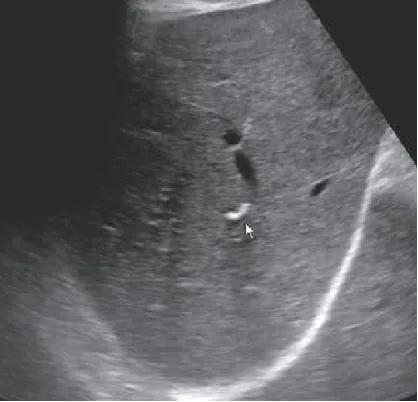

交通性海绵状胆管扩张(Caroli病)

● 定义:指肝内末梢胆管的葡萄串样囊状扩张,定义为肝内胆管非梗阻性节段性的囊状或梭状扩张,不伴有胰胆管合流异常。

● 超声表现:肝内沿胆管走行分布、多发的与胆管相通的无回声,可以弥漫性,也可以局限性的;特征性的表现为囊状扩张的胆管内见小圆点状高回声。